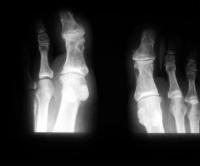

Kristallarthropathie - Tophöse Gicht

Abbildung 2: Tophöse Gicht – Röntgen.